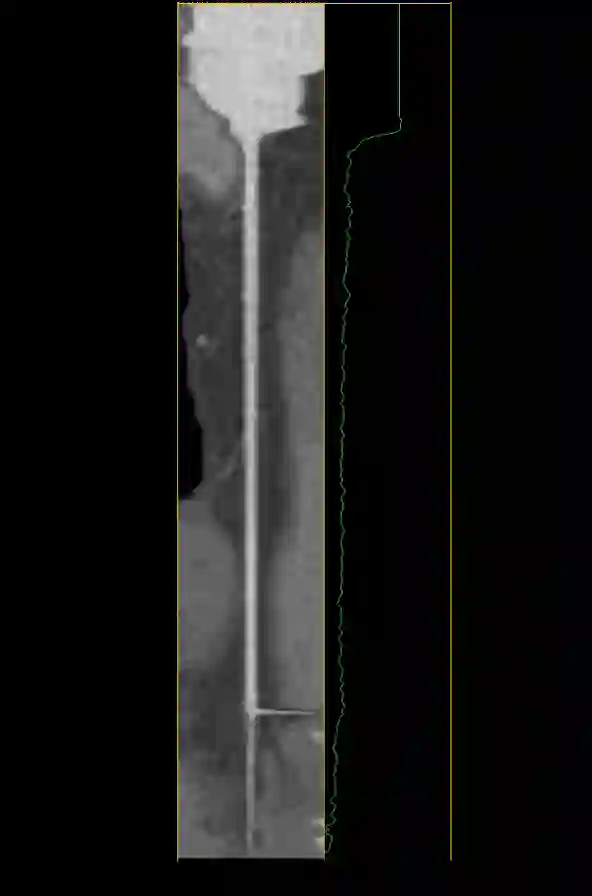

The standard non-invasive imaging technique used to assess the severity and extent of Coronary Artery Disease (CAD) is Coronary Computed Tomography Angiography (CCTA). However, manual grading of each patient's CCTA according to the CAD-Reporting and Data System (CAD-RADS) scoring is time-consuming and operator-dependent, especially in borderline cases. This work proposes a fully automated, and visually explainable, deep learning pipeline to be used as a decision support system for the CAD screening procedure. The pipeline performs two classification tasks: firstly, identifying patients who require further clinical investigations and secondly, classifying patients into subgroups based on the degree of stenosis, according to commonly used CAD-RADS thresholds. The pipeline pre-processes multiplanar projections of the coronary arteries, extracted from the original CCTAs, and classifies them using a fine-tuned Multi-Axis Vision Transformer architecture. With the aim of emulating the current clinical practice, the model is trained to assign a per-patient score by stacking the bi-dimensional longitudinal cross-sections of the three main coronary arteries along channel dimension. Furthermore, it generates visually interpretable maps to assess the reliability of the predictions. When run on a database of 1873 three-channel images of 253 patients collected at the Monzino Cardiology Center in Milan, the pipeline obtained an AUC of 0.87 and 0.93 for the two classification tasks, respectively. According to our knowledge, this is the first model trained to assign CAD-RADS scores learning solely from patient scores and not requiring finer imaging annotation steps that are not part of the clinical routine.